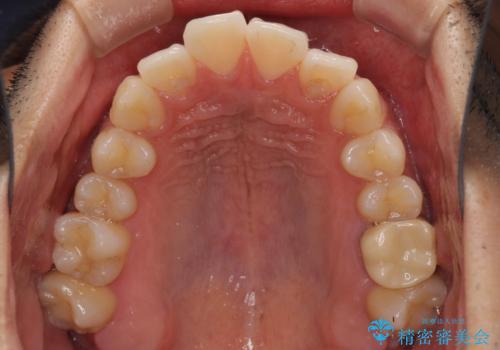

前歯のデコボコを治したい インビザライン矯正治療

- 前歯のデコボコを治したいとのことで来院された患者様です。

上下顎ともに歯列全体の後方移動とIPR(歯と歯の間を削る)によってデコボコが解消するように設計し、インビザラインにより治療を行うこととしました。

毎日22時間以上しっかりとマウスピースを装着していただいたので、スムーズに治療が進みました。歯と歯の間を削ることでうまくスペースコントロールでき、1年強で終えることができました。